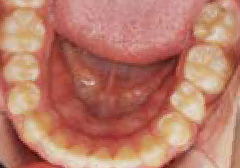

でこぼこ

口呼吸から鼻呼吸、食べ方や飲み込み方で歯並びは良くなる!

Nさん (矯正開始時:8歳)

Before

After

上の前歯がゆがみ下の歯が内側に傾いています。舌の位置が悪く、口を開けたまま食べ物を飲み込む癖がありました。また、口をポカンと開けてテレビを見ていることが多いなど、鼻づまりによる口呼吸特有の症状が見られました。

治療を終えて

装置によって上あごを広げ前歯をきれいに並べました。下の歯の位置も整えました。歯がしっかりと咬み合うようになり、舌の位置や鼻の通りも良くなりました。気道も広がったことで、口呼吸が改善されました。

主訴・治療内容 でこぼこの歯で、将来の歯並びが心配と来院されましたが、呼吸法やお口の使い方が原因と、丁寧に説明させていただきました。

治療期間 2年半

費用 495,000円(税込)